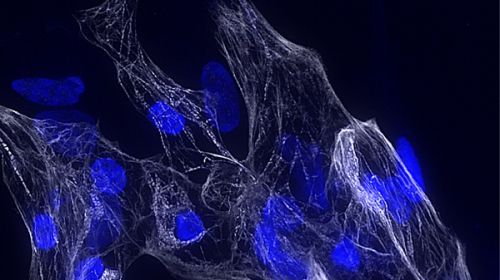

Identificato per la prima volta nell’essere umano un gene finora sconosciuto, che tuttavia ha un ruolo cruciale nella maturazione dei cardiomiociti, le cellule responsabili della contrazione cardiaca. La scoperta è di un gruppo di ricerca del Dipartimento di biologia e biotecnologie ‘Charles Darwin’ della Sapienza Università di Roma in collaborazione con l’Istituto di biologia e patologia molecolari del Consiglio nazionale delle ricerche (Cnr-Ibpm) di Roma. La scoperta è stata pubblicata sulla rivista Nature Communications.

Lo studio ha rivelato come il malfunzionamento di questo gene, battezzato HSCHARME, sia associato a cardiomiopatie in diverse coorti di pazienti, aprendo nuove prospettive per diagnosi più precise e terapie mirate.“Questo gene appartiene alla categoria dei cosiddetti RNA non codificanti lunghi (lncRNA), molecole che non danno origine a proteine ma regolano finemente l’attività di altri geni”, afferma la prof.ssa Monica Ballarino della Sapienza Università di Roma. “HSCHARME agisce come un vero e proprio ‘architetto’ del genoma che guida la corretta attività dei geni del cuore. HSCHARME si è rivelato cruciale per guidare lo sviluppo e la maturazione dei cardiomiociti, le cellule muscolari responsabili della contrazione cardiaca. Quando questo gene non funziona correttamente, le cellule non si sviluppano in maniera adeguata, con conseguenze sulla salute dell’intero organo”.

Il risultato è stato reso possibile grazie a un insieme di tecnologie d’avanguardia, dalla genomica comparativa alla trascrittomica a singola cellula, fino al genome editing e all’uso di cellule staminali pluripotenti indotte, differenziate in cardiomiociti umani. Grazie a questi strumenti i ricercatori hanno ricostruito i partner molecolari del gene e ne hanno studiato la funzione in modelli cellulari e in campioni clinici, individuando la proteina PTBP1 come cofattore fondamentale.